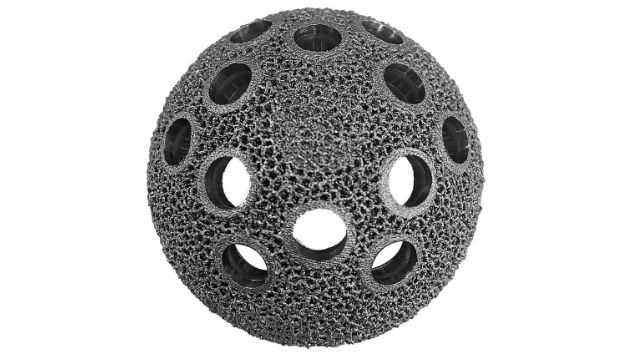

–Ъ–Њ–Љ–њ–Њ–љ–µ–љ—В—Л –≤–µ—А—В–ї—Г–ґ–љ–Њ–є –≤–њ–∞–і–Є–љ—Л MH